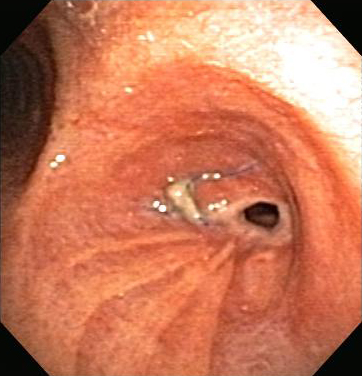

Post-lung transplant anastomotic bronchial stenosis

From the collections of Jose Fernando Santacruz MD, FCCP, DAABIP and Erik Folch MD, MSc; used with permission